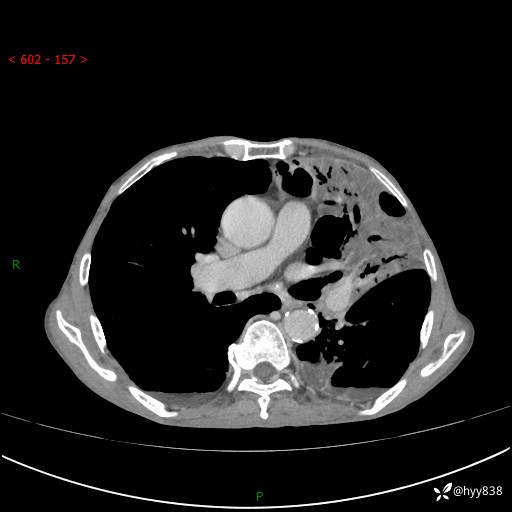

胸部CT平扫+增强